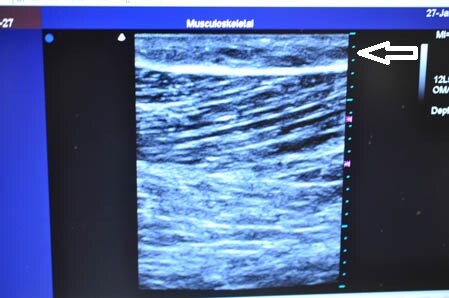

画像上しっかりと皮下脂肪は根こそがれており

間違いなく患者様のご期待にはそえられると思います。